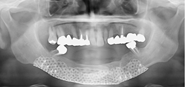

下顎骨の腫瘍で下顎を切除し(写真左)、切除したところを腰骨で再建し(写真中央)、インプラントを支えにしたブリッジ(写真右、白い部分)でかめるようにした症例のエックス線写真